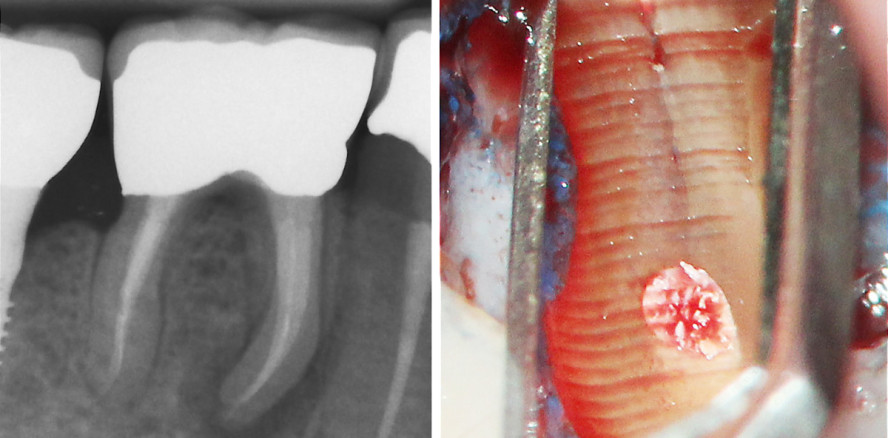

Gruppe 3: Prämolaren – Abb. 5: Zahnfilme vor der Operation der Fälle 1–6. © Dr. Bernhard Albers

Gruppe 3: Prämolaren – Abb. 6: Fotos der angefärbten Resektionsfläche der Fälle 1–6. © Dr. Bernhard Albers

Gruppe 3: Prämolaren (Abb. 5 und 6)

Im Fall 6 lag eventuell eine etwas zu kurze Wurzelfüllung vor, im Fall 4 eine inhomogene infizierte Wurzelfüllung. In den anderen vier Fällen mit jeweils zwei Kanalsystemen pro Wurzel gab es jeweils infizierte nicht abgefüllte Hohlräume und/oder Isthmen.